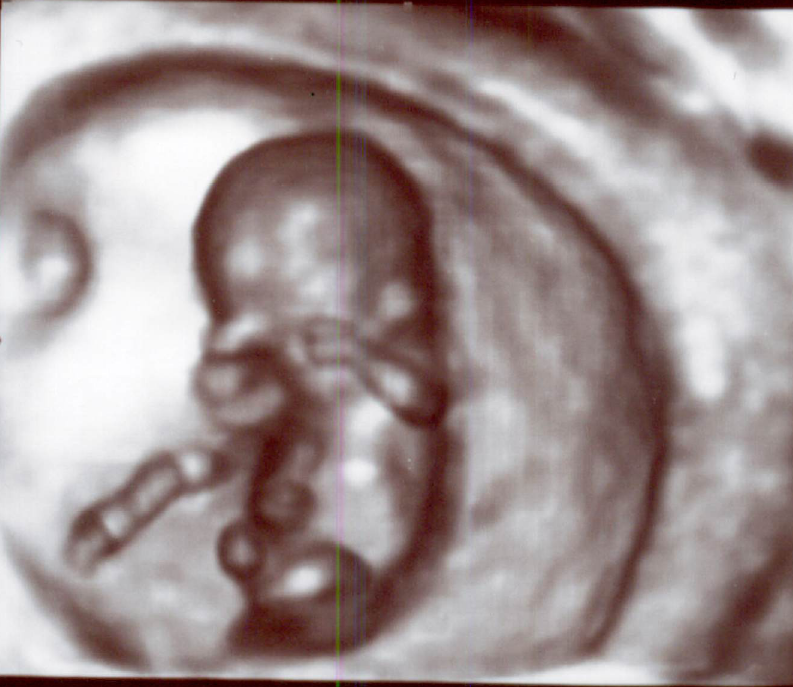

①子宮内妊娠か、子宮外妊娠か:

まず、子宮内に妊娠していることを、超音波で確認します。子宮外妊娠の場合では、ほとんどが卵管に妊娠します。

②胎児の大きさは、標準の大きさか:

超音波で診ます。胎児の標準の大きさについては「02】妊娠初期:₀₆₎胎児の標準の大きさ」をご覧ください。